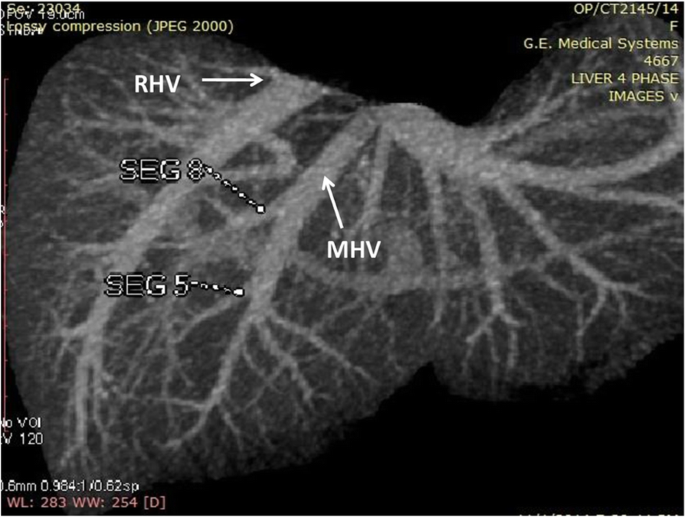

Hepatic Veins: Two inferior right hepatic veins measuring 4.1 mm and 4.5 mm in diameter were noted draining into inferior vena cava. Significant size segment V (3.4 mm) and VIII (2.8 mm) veins were draining into MHV (Figs. 3 and 4).

-